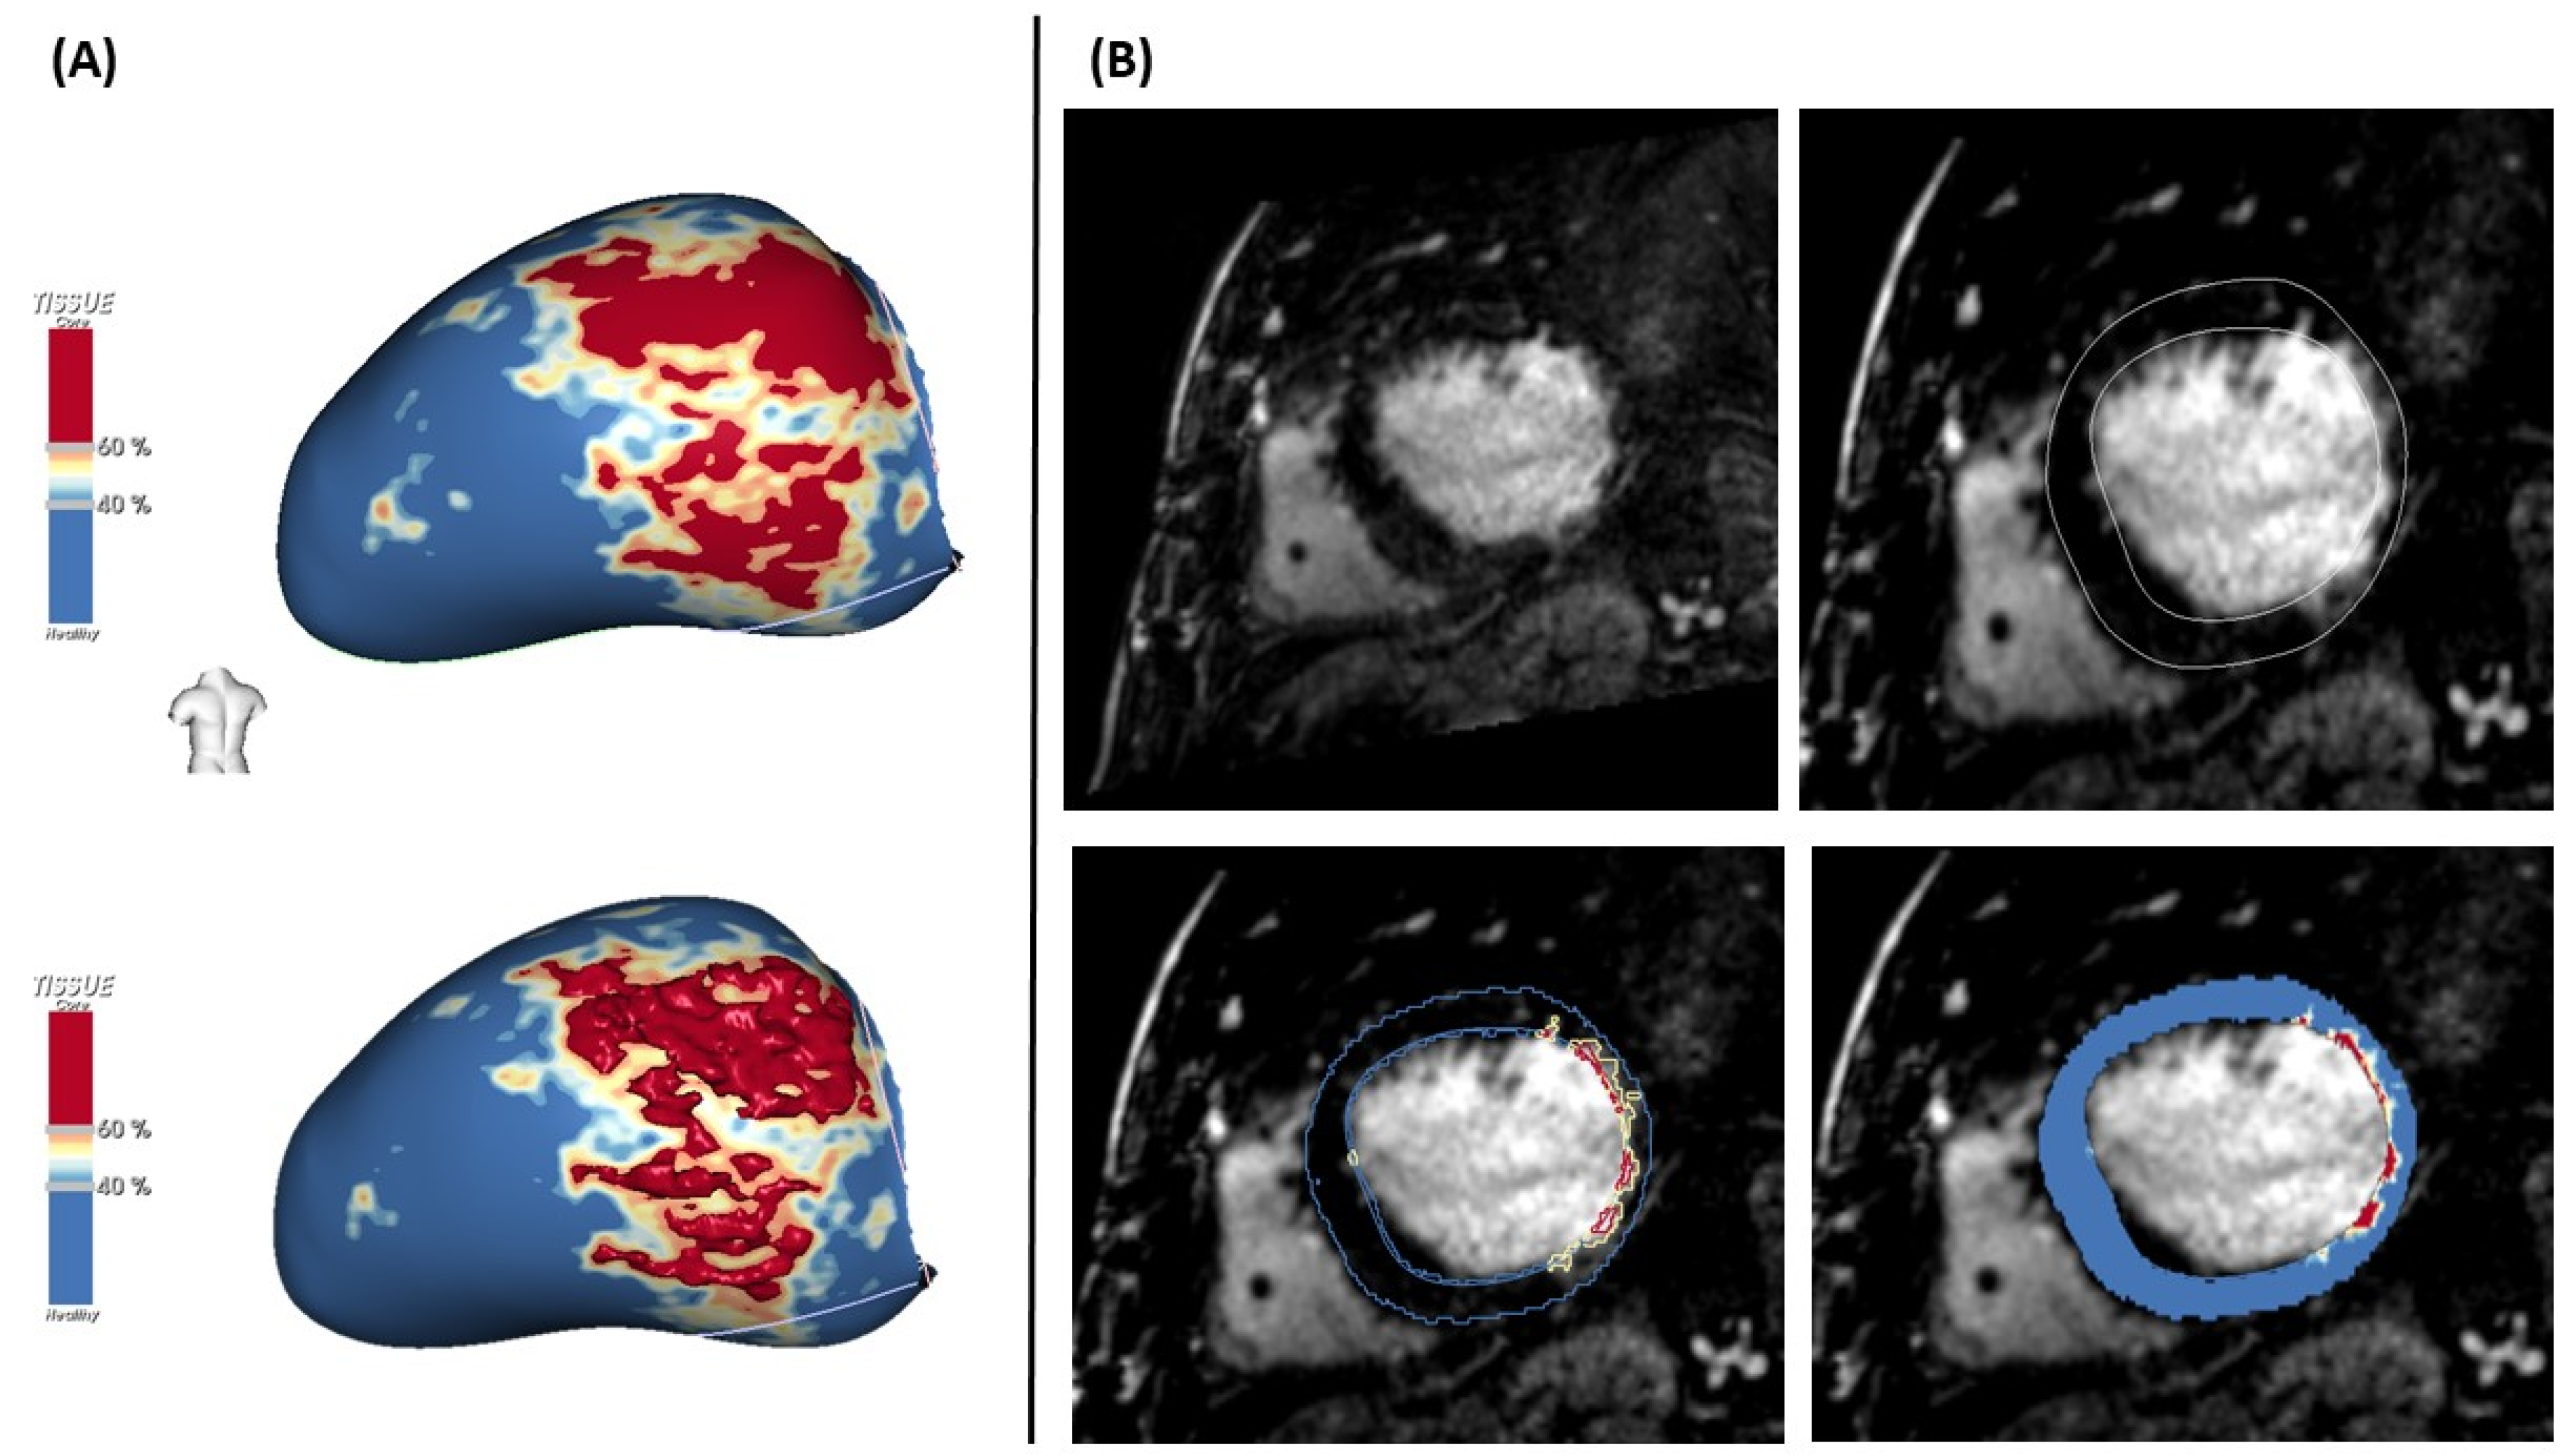

4.5. LGE-MRI for VT Ablation

- Andreu, D.; Berruezo, A.; Ortiz-Pérez, J.T.; Silva, E.; Mont, L.; Borràs, R.; de Caralt, T.M.; Perea, R.J.; Fernández-Armenta, J.; Zeljko, H.; et al. Integration of 3D electroanatomic maps and magnetic resonance scar characterization into the navigation system to guide ventricular tachycardia ablation. Circ. Arrhythm. Electrophysiol. 2011, 4, 674–683. [Google Scholar] [CrossRef] [Green Version]

- Fernandez-Armenta, J.; Berruezo, A.; Andreu, D. Threedimensional architecture of scar and conducting channels based on high resolution ce-CMR: Insights for ventricular tachycardia ablation. Circ. Arrhythm. Electrophysiol. 2013, 6, 528–537. [Google Scholar] [CrossRef] [Green Version]

- Piers, S.R.D.; Tao, Q.; De Riva Silva, M.; Siebelink, H.M.; Schalij, M.J.; Van Der Geest, R.J.; Zeppenfeld, K. CMR-based identification of critical isthmus sites of ischemic and nonischemic ventricular tachycardia. JACC Cardiovasc. Imaging 2014, 7, 774–784. [Google Scholar] [CrossRef] [Green Version]

- Andreu, D.; Ortiz-Perez, J.T.; Boussy, T.; Fernandez-Armenta, J.; Caralt, T.M.; Perea, R.J. Usefulness of contrast-enhanced cardiac magnetic resonance in identifying the ventricular arrhythmia substrate and the approach needed for ablation. Eur. Heart. J. 2014, 35, 1316–1326. [Google Scholar] [CrossRef] [Green Version]

- Acosta, J.; Fernández-Armenta, J.; Penela, D.; Andreu, D.; Borras, R.; Vassanelli, F.; Korshunov, V.; Perea, R.J.; de Caralt, T.M.; Ortiz, J.T.; et al. Infarct transmurality as a criterion for first-line endo-epicardial substrate-guided ventricular tachycardia ablation in ischemic cardiomyopathy. Heart Rhythm 2016, 13, 85–95. [Google Scholar] [CrossRef] [Green Version]

- Quinto, L.; Sanchez, P.; Alarco, F.; Garre, P.; Zaraket, F.; Prat-gonzalez, S. Cardiac magnetic resonance to predict recurrences after ventricular tachycardia ablation: Septal involvement, transmural channels, and left ventricular mass. Europace 2021, 23, 1437–1445. [Google Scholar] [CrossRef]